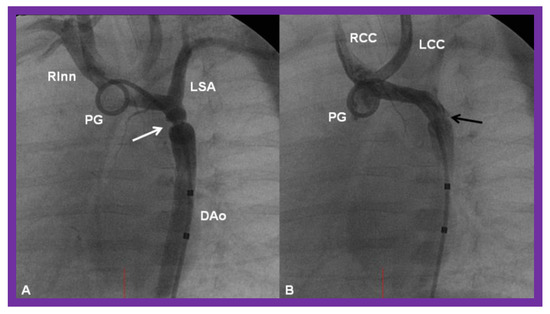

Cineangiographic frames from aortic arch angiograms in a 20° left anterior oblique views, illustrating a narrowed (coarcted) aortic segment (arrow) priot to balloon angioplasty (A) which improved following balloon angioplasty (B). Note mild hypoplasia of the distal transverse aortic arch and isthmus. AAo, ascending aorta; DAo, descending aorta; LCC, left common carotid artery; LSA, left subclavian artery; NG, nasogastric tube; PG, pigtail catheter; RInn. right innominate artery. Modified from Reference [90].

Figure 24.

Cineangiographic frames from aortic arch angiograms in 20° left anterior oblique projection, illustrating a coarcted aortic segment (white arrow) prior to balloon angioplasty (A) which widened (black arrow) following balloon angioplasty (B) in a neonate who had had the Norwood procedure earlier. DAo, descending aorta; LCC, left common carotid artery; LSA, left subclavian artery; PG, pigtail catheter; RCC, right common carotid artery; RInn, right innominate artery. Reproduced from Reference [58].

Figure 25.